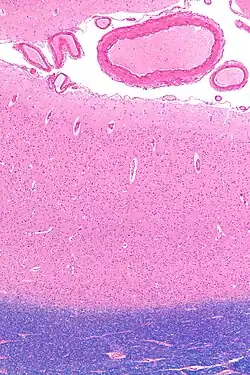

Micrograph showing the visual cortex (predominantly pink). Subcortical white matter (predominantly blue) is seen at the bottom of the image. HE-LFB stain.